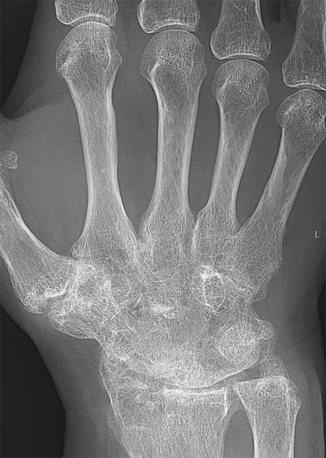

类风湿性关节炎

类风湿性关节炎是免疫系统攻击关节滑膜引起的。当关节发炎时,免疫系统通常会采取此应对方式。但就类风湿性关节炎而言,这会导致本该活动自如的部位产生剧痛,并变僵硬。

从患者的 X 光片可看出患者的腕骨融合在一起。若长期罹患类风湿性关节炎就可能出现此症状。